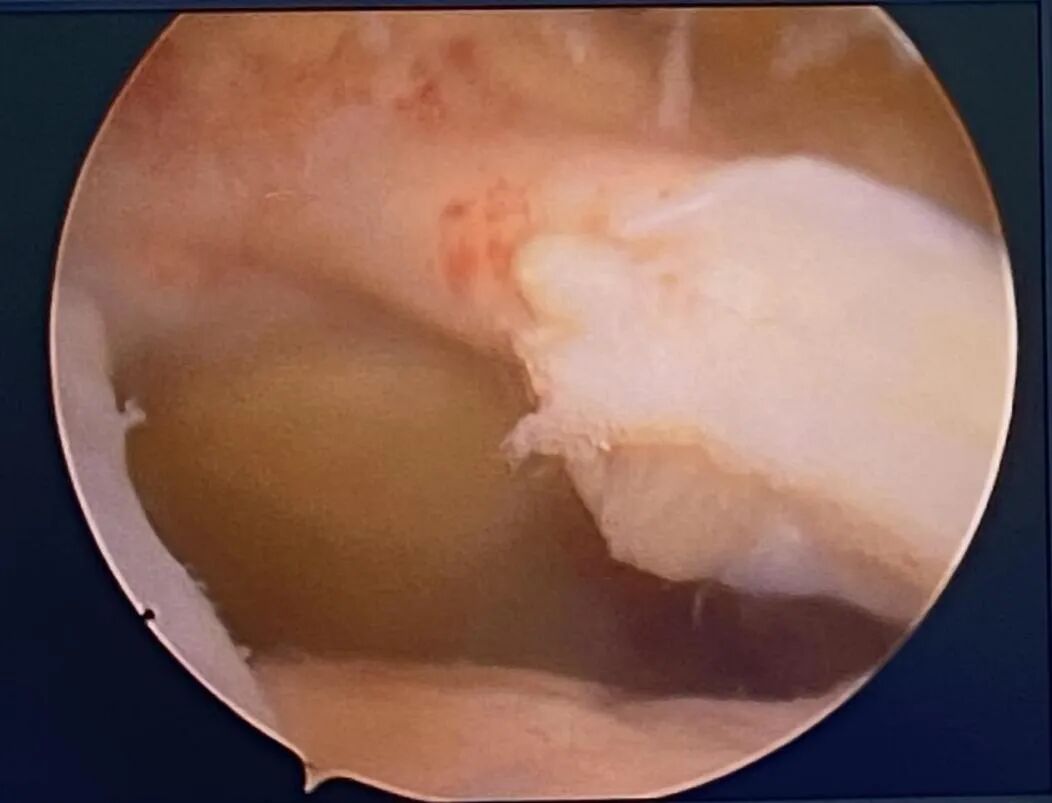

术中,医生在关节镜下探查可见肱骨头明显上移,冈上肌、冈下肌全层撕裂并严重回缩,残余肌腱纤薄并有脂肪浸润,肱二头肌长头腱炎性改变且部分磨损。在关节镜下,医生用2枚锚钉将肱二头肌腱长头转位固定。在对侧的下肢截取桥接移植物——半腱肌肌腱,镜下将移植物引入关节腔并以2枚锚钉牢固固定于大结节,至此手术已接近尾声,总共用时仅60分钟。此后于肩胛冈内侧解剖游离斜方肌下束,并通过相关器械将移植物的另一端传递到内侧切口与斜方肌下束以Krackow法编织缝合固定。术后探查移植物固定可靠,盂肱关节恢复正常对合关系。

术中打入肩关节外排锚钉,固定移植肌腱。